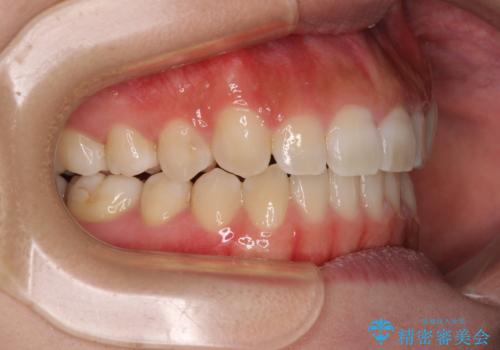

上顎骨を拡大することで、八重歯やデコボコを歯列に収めることができ、下顎の歯が外に位置していた奥歯の咬み合わせも改善することができました。

スペースも短期間に獲得できるため、1年程度で治療を終えることができました。